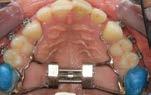

SPINA BIFIDA IS A CONGENITAL CONDITION AFFECTING THE SPINAL CORD AND POSES SIGNIFICANT CHALLENGES FOR PATIENTS AND THEIR FAMILIES. IT OCCURS WHEN THE SPINAL CORD DOES NOT DEVELOP PROPERLY DURING FOETAL DEVELOPMENT. THIS CONDITION CAN LEAD TO VARIOUS IMPAIRMENTS, INCLUDING DIFFICULTIES WITH MOBILITY, BOWEL AND BLADDER DYSFUNCTION, AND LOSS OF SENSATION.

JULY.AUG 2023 8